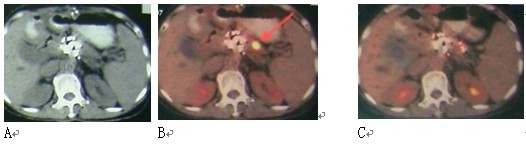

图4 女性,61岁。胰腺颈部3X3cm病变,活检显示腺癌。肝内有3个转移灶(图中未显示)。A:治疗前;B:冷冻加125碘粒子植入治疗,7个月后复查,胰腺和肝内无明显癌肿证据(肝内病变未显示)。患者迄今已生存4年。

图5 女性,64岁。胰腺头部肿块,活检显示鳞癌。给予冷冻加碘粒子植入。A:治疗前;B:治疗后8个月复查。患者生存14个月。

图6 微血管介入与冷冻、碘粒子植入的相辅相成作用。 图示左肺癌,冷冻加125碘粒子植入一周,血管造影在肿瘤周边区仍有肿瘤血管染色(A),通过微导管注入微颗粒化疗药(CMI),原先血管染色大部消失